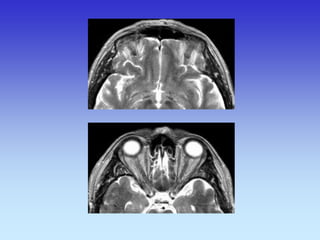

PARANAZALNI SINUSI i ORBITE

CT- ORBITA

TRANSVERZALNI SLOJ